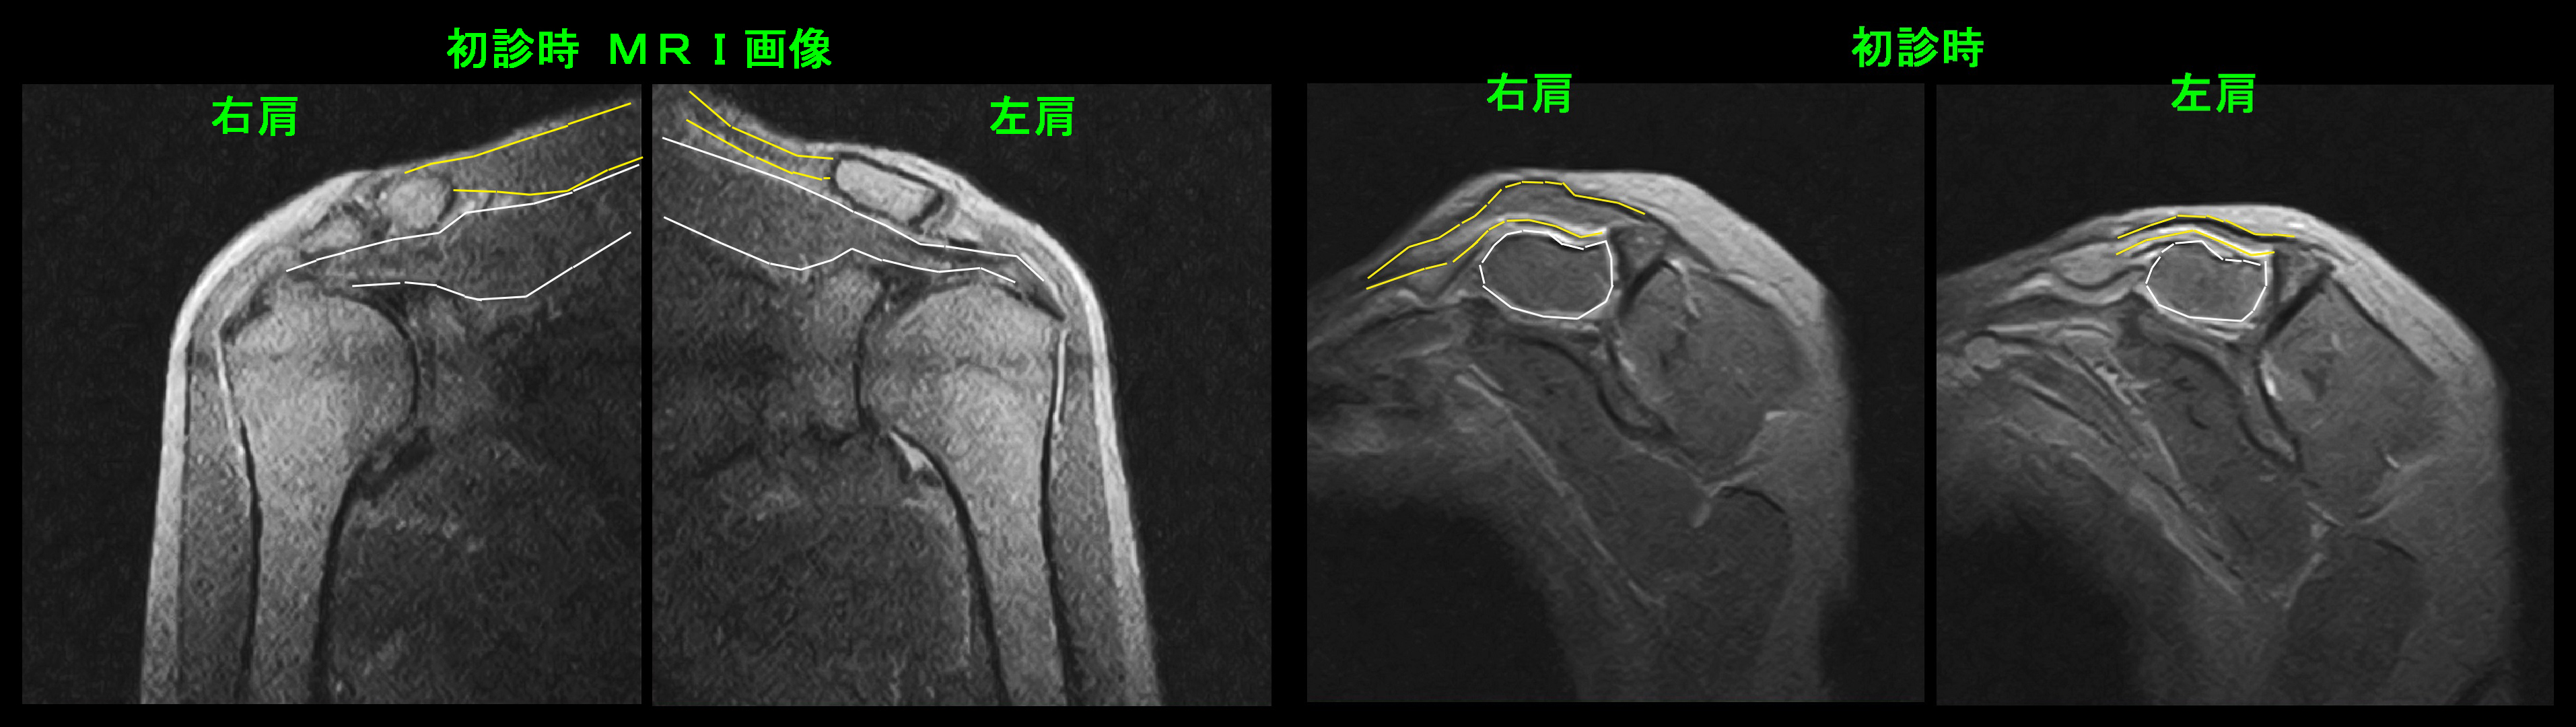

MRI検査では白線は肩甲骨棘上筋という筋で、黄色線が僧帽筋となりますが、左僧帽筋は右に比して薄くなって麻痺によって萎縮してしまったことが分かります。

初診時の左肩の状態ですが、十分な挙上とはなっていません。

初診時の両側のレントゲン像ですが、肩甲骨は白線で囲っています。左肩甲骨は頭部側に偏位していて、縦の長さも短縮しています。